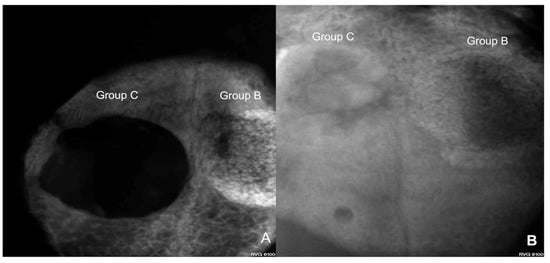

Figure 6 and Figure 7 show the condensation of more homogeneous dentin grafts in rabbits’ skulls at four and eight weeks compared with BTCP ®.

Figure 7. (A) Digital image of a rabbit skull showing more bone formation around the human sterilized crushed teeth graft (Group B) compared with the control group (Group C) at four weeks of evaluation; (B) at eight weeks, the dentin graft group (Group B) showed a lateral calcified area compared with slightly spontaneous bone healing in Group C.